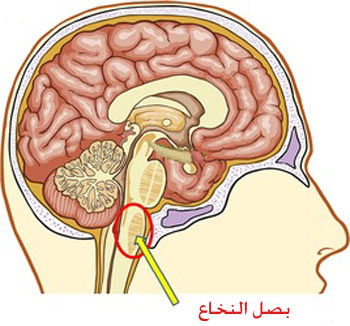

قیمت: 48٬000 تومان - دسته بندی فایل: علوم پزشکیپاورپوینت بصل النخاع MEDULLA OBLANGATA

فروش ویژه پاورپوینت حرفه ای بصل النخاع MEDULLA OBLANGATA با تخفیف استثنایی فقط 51 هزار تومان تعداد اسلاید: 31 اسلاید